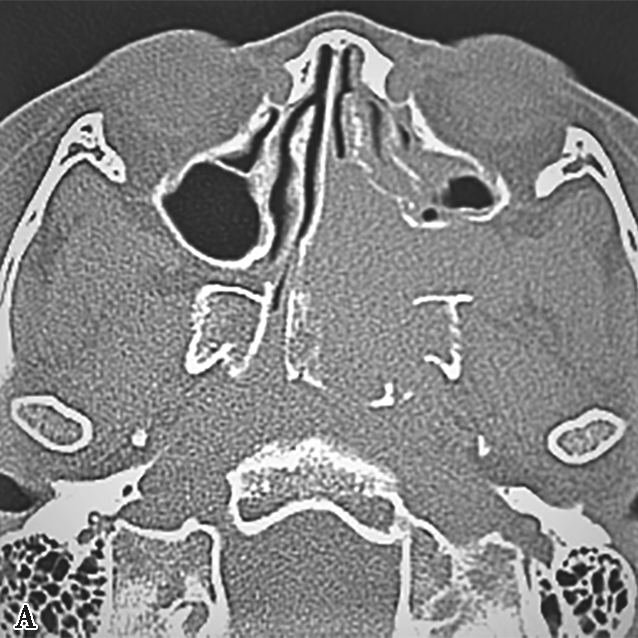

图1-2-4 青少年鼻咽纤维血管瘤

患者男,12岁,间断鼻出血1年。A.鼻窦CT横断面骨窗,示左侧蝶腭孔扩大,被不规则软组织肿块占据,病变累及左侧鼻腔、鼻咽、翼腭窝,邻近骨质可见溶骨性骨质破坏;B.鼻窦CT冠状面重组骨窗,示病变累及鼻腔、蝶窦,邻近骨质可见溶骨性骨质破坏;C.鼻咽部MR T 2 WI横断面,示左侧鼻咽、鼻腔不均匀等信号肿块,病变通过扩大蝶腭孔累及翼腭窝,病变内可见多发血管流空信号;D.鼻咽部MR T 1 WI横断面,示病变呈不均匀低信号;E.鼻咽部MR T 1 WI横断面增强+脂肪抑制序列横断面,示病变显著不均匀信号,与邻近组织分界尚清